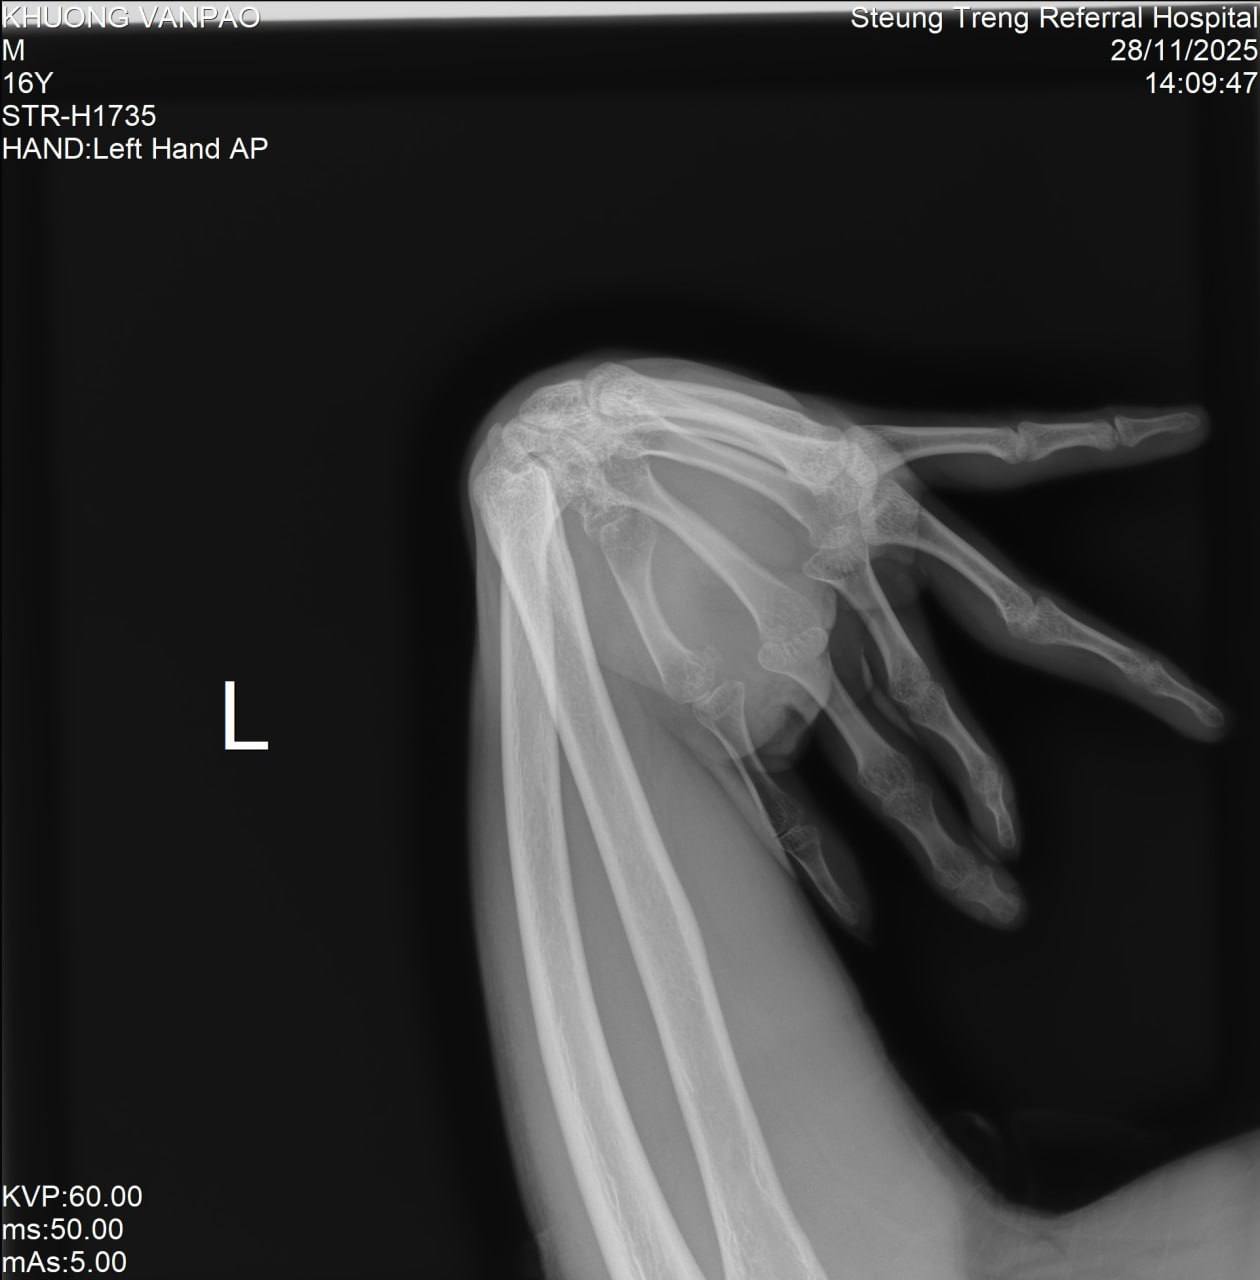

ឯកឧត្តមនាយកមន្ទីរពេទ្យកុមារជាតិនិងឯកឧត្តមប្រធានក្រុមប្រឹក្សាភិបាលនៃសម្ព័ន្ធគ្រូពេទ្យ សសយក បានអនុញ្ញាត្តិអោយលោកវេជ្ជបណ្ឌិត កែវ វណ្ណា នាយករងមន្ទីរពេទ្យកុមារជាតិ បានដឹកនាំក្រុមគ្រូពេទ្យវះកាត់នៃមន្ទីរពេទ្យកុមារជាតិ បំពេញបេសកកម្មមនុស្សធម៍វះកាត់កុមារដែលមានជំងឺ ក្លនលូន ឆែបមាត់ ឆែបក្រអូម ប្រដាប់ភេទខុសប្រក្រតី ដុំពក ពិការអវយវះពីកំណើត ដោយរលាក របួស និងជំងឺត្រចៀក ច្រមុះបំពង់ក នៅមន្ទីរពេទ្យបង្អែកខេត្តស្ទឹងត្រែង ក្រោមការជួយយឧបត្ថម្ភគាំទ្រដោយអភិបាលនៃគណអភិបាលរដ្ឋបាលខេត្ត ស្ទឹងត្រែង បានចំនួន 104 ករណី និងពិនិត្យជំងឺកុមារបាន 353នាក់ ព្រមទាំងបញ្ជូនមកបន្តវះកាត់នៅមន្ទីរពេទ្យកុមារជាតិចំនួន 5នាក់។